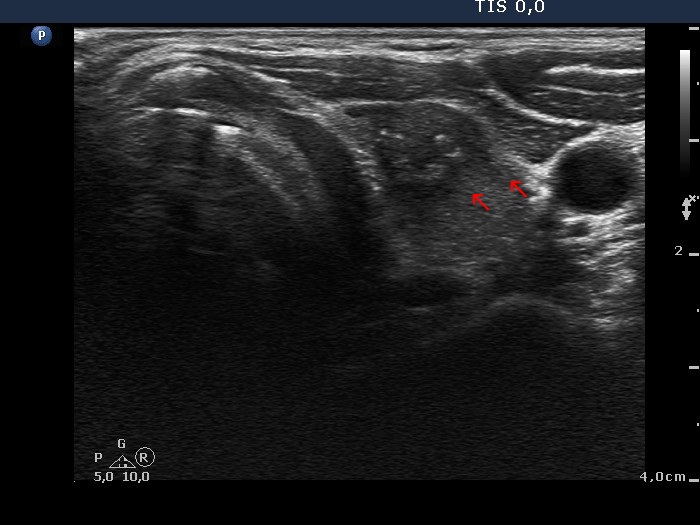

Transverse scan |

The lesion has partly blurred and partly spiculated margins. Although this presentation corresponds to thyroiditis, the fact that there are one or two relatively large lesions in the lobe should raise the possibility of nodular origin, namely papillary carcinoma. (Three types of indistinct borders are presented in these images. Green arrows point to that part of the nodule which echogenicity is identical to the extrathyroidal strap muscle. The tumor has partly blurred (red arrows) and partly spiculated (yellow arrows) margins. The extent of blurred part of the border exceeds 50%.)